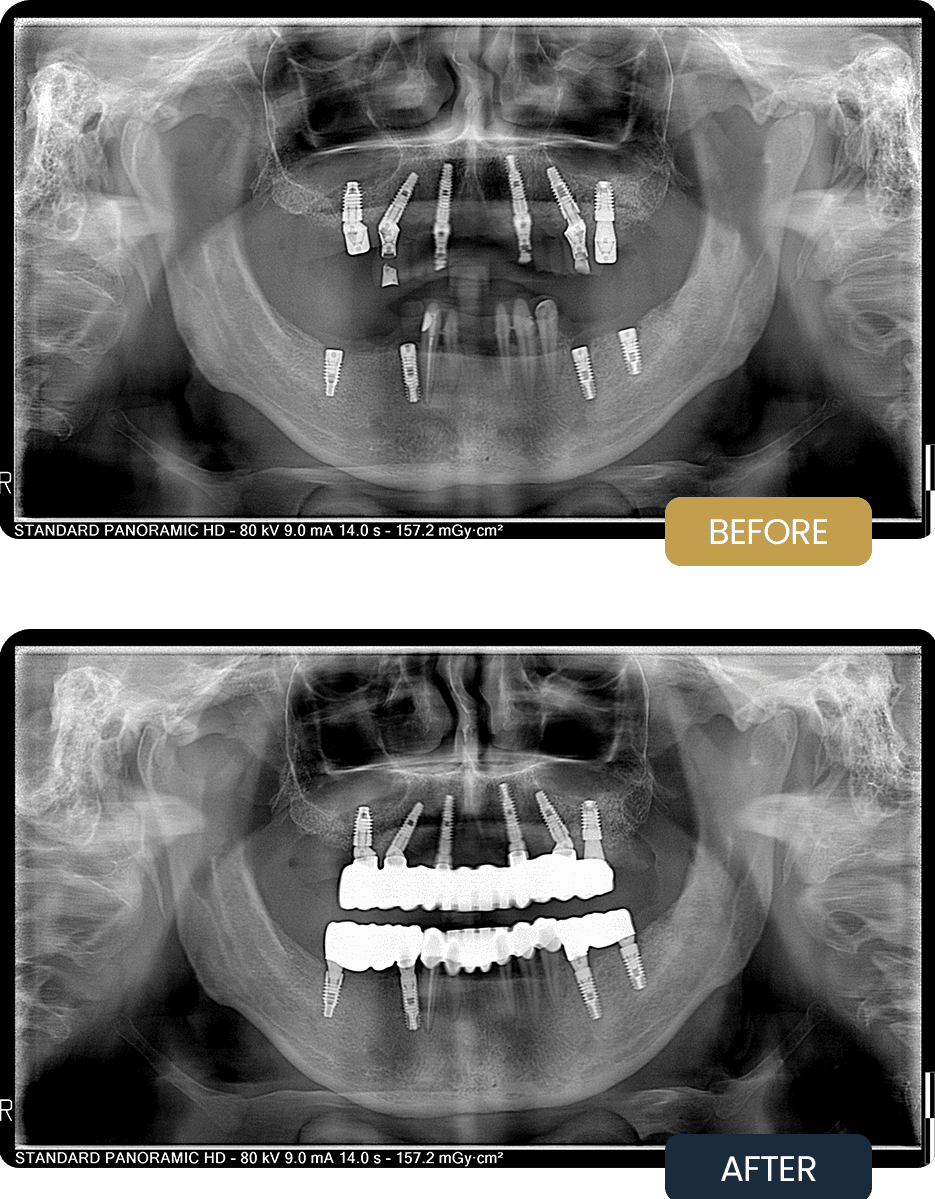

• Upper Jaw: All on 6 Implant Rehabilitation

• Lower Jaw: 4 Dental Implants

• Lower Jaw: 12 Dental Crowns

In the upper jaw, an All on 6 implant concept was selected, with six strategically placed implants to support a fixed full arch prosthesis and ensure optimal load distribution and long term stability.

In the lower jaw, four dental implants were placed to replace missing teeth and provide stable support. Twelve dental crowns were then planned to restore tooth form, alignment, and occlusion, creating a balanced and functional bite across both arches.

Panoramic imaging confirmed the need for full arch implant rehabilitation in the upper jaw and implant supported crown restoration in the lower jaw to restore strength, function, and long term predictability.

Post treatment panoramic imaging confirmed stable implant placement in both jaws and accurately seated implant supported restorations.

The final prostheses restored proper bite alignment, improved chewing comfort, and delivered a stable, natural looking result with long term functional reliability.